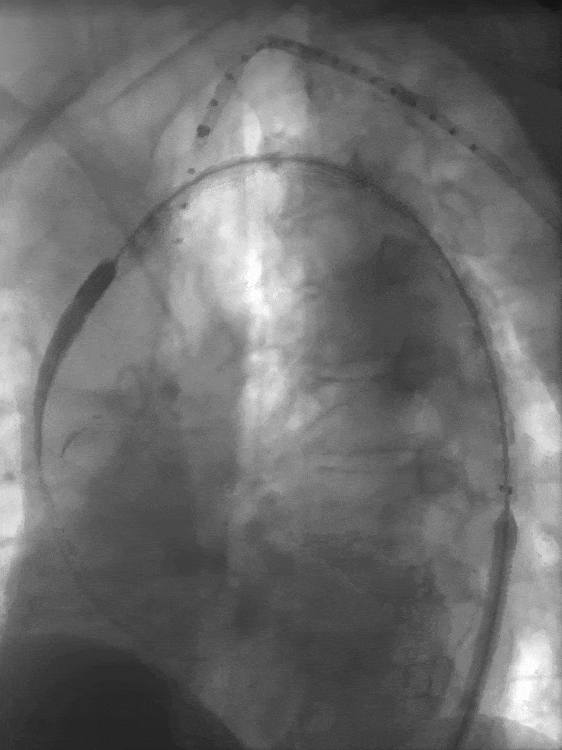

1. 患者仰卧位,常规消毒,铺无菌单,全麻成功后穿刺右侧股动脉,引入短鞘备用;切开左侧肱动脉,穿刺引入导丝,置入8.5F可调弯鞘,引导金标猪尾造影导管至升主动脉水平造影示主动脉弓部巨大瘤样扩张,与术前CT一致。

LAO造影

RAO造影

2. 术中精准测量左颈总动脉根部远端处主动脉直径,确定华脉泰科胸主动脉覆膜支架型号。右侧股动脉引入超硬导丝,退出金标猪尾导管,送入华脉胸主覆膜支架系统,精准定位于左颈总根部远端位置,释放2-3节,再次确认位置无误后,释放全部支架及后释放裸支架,再次造影示:支架位置精准、展开良好,未见成角畸形,左颈总动脉血供良好,无明显内漏。

置入华脉胸主支架

近端定位LCCA根部远端

缓慢释放2节再次确认位置

全部释放支架